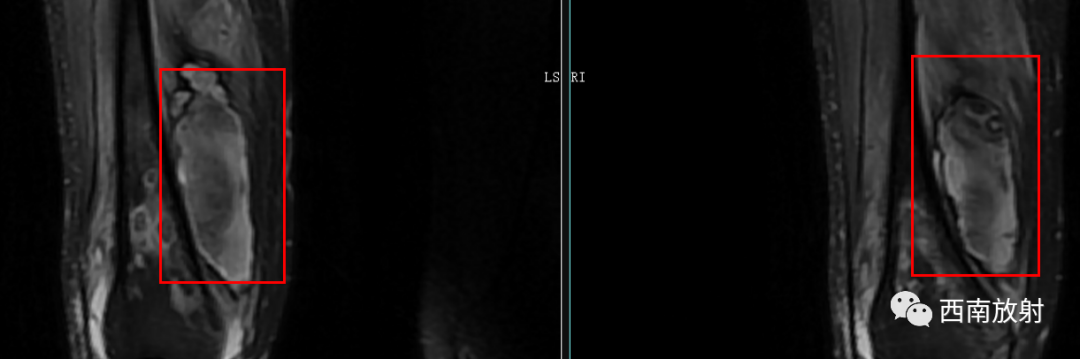

CT显示骨破坏、脓肿、死骨及骨膜增生、骨质增生硬化,呈骨小梁密度增高、模糊,髓腔密度增大、狭窄,皮质增厚。MRI显示早期骨髓内广泛分布的斑片异常信号,与邻近正常骨髓信号相比较,T1WI信号减低,T2WI信号增高,脂肪抑制T2WI 或STIR 等序列上病变显示更清楚,骨皮质周围软组织内呈弥漫分布的T1WI低信号及T2WI高信号影,边界模糊。出现骨膜反应,骨皮质不规则破坏,脓肿及死骨形成。

▲软组织脓肿

▲MRI脂肪征:病灶内单发或多发,T1WI上呈高信号,脂肪抑制序列信号明显减低。急性骨髓炎的脂肪球征发生机制:骨髓炎的炎性反应致骨髓腔内充血、渗出及水肿最终导致髓内压力增高,髓腔内大量脂肪细胞(即髓脂细胞)快速坏死释放出游离脂质并聚集形成脂肪球[2-3]。